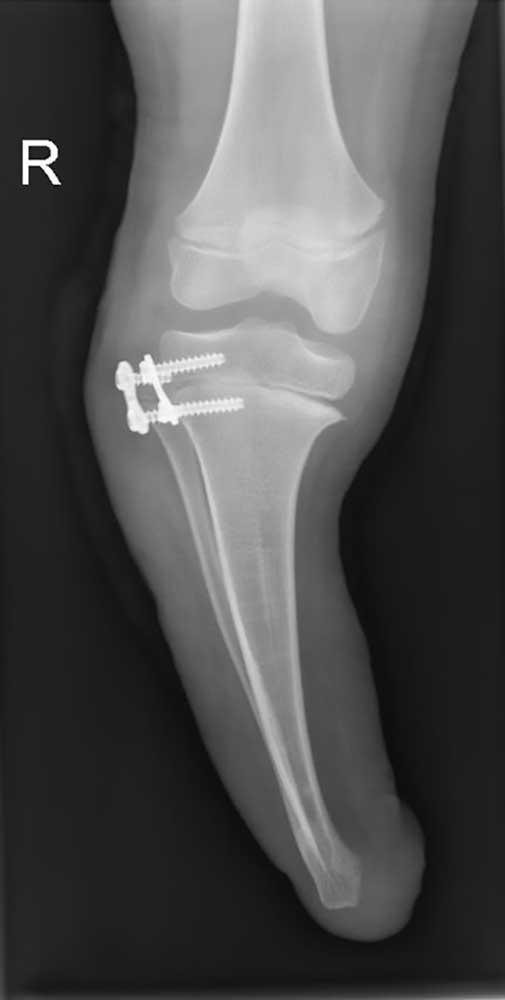

Ein 12-jähriger Patient weist eine Unterschenkel-Dysmelie und eine Varusfehlstellung des Stumpfes auf. Im Alter von 13 Jahren wurden eine Epiphyseodese der proximalen lateralen Tibia und eine Fibula-Epiphyse durchgeführt (Abb. 1a). Nach Wachstumsabschluss zeigt sich weiterhin eine varische Unterschenkelachse, insbesondere im distalen Anteil (Abb. 1b). Die Beinachse kann zwar durch die orthoprothetische Versorgung bzw. den korrekten Aufbau berücksichtigt werden, es entsteht jedoch rezidivierend eine Druckstelle am Stumpfpol sowie lateral an der proximalen Fibula durch mechanische Überbelastung (Abb. 1c). Daraus resultieren massive funktionelle Einschränkungen und letztlich die Indikation zur Stumpfrevision; dadurch kann die mechanische Belastung auf den Stumpf reduziert und gleichzeitig funktionell die Beinachse korrigiert werden.